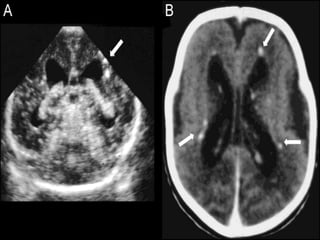

The classic triad of findings :

chorioretinitis,

 hydrocephalus, and

 intracranial calcifications

Transplacental infection can result in :

 intrauterine growth restriction,

 Sensorineural hearing loss,

 Intracranial calcifications,

 Jaudice

 Petichiae

 microcephaly,

 hydrocephalus,

 hepatosplenomegaly,

 Delayed psychomotor development,

 Thrombocytopenia and/

 Chorioretinitis .